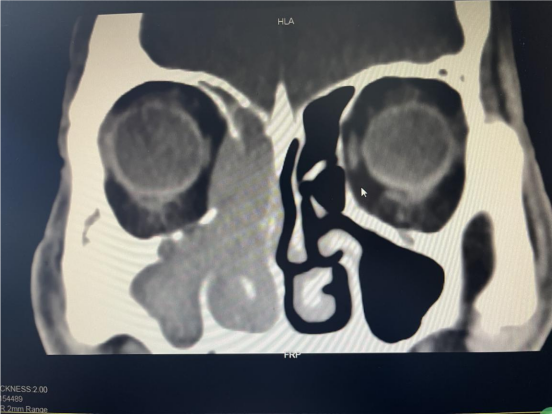

(鼻窦CT)

住院后更全面、精准的检查后,发现老人鼻子里的肿块已经靠近眼睛和颅底,而肿块活检报告也和预估一致:鼻恶性肿瘤。随后,由章程副院长、赵礼君主任领衔的医疗团队进行了数次讨论,结合目前学科诊疗进展,一致认为手术+术后进一步治疗是最有效、最值得推荐的治疗方案。"对于高龄患者,我们不仅要考虑手术本身,更要全面评估其身体承受能力,确保治疗安全。"耳鼻喉科主任医师章程介绍。